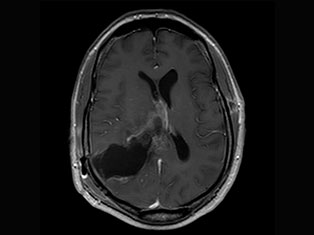

Cerebro Vascular

A stroke occurs when the blood supply to part of your brain is interrupted or reduced, preventing brain tissue from getting oxygen and nutrients. Brain cells begin to die in minutes. A stroke is a medical emergency.